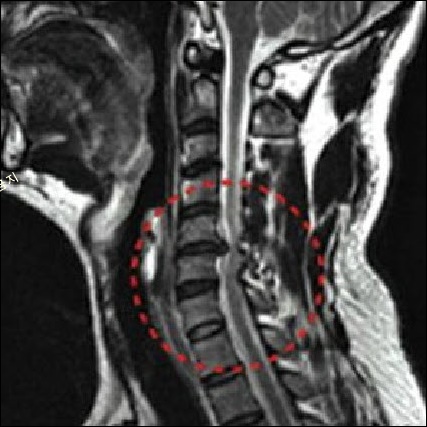

경추(목뼈)는 총 7개의 뼈로 구성되어 있으며, 경추 사이에 충격을 흡수하는 연골 조직인 추간판(디스크)이 있습니다.

추간판이 후방으로 탈출하면 신경을 압박하여 통증을 유발하게 되는데, 이를 보통 '목 디스크'라고 합니다. 목디스크가 발병하면 목이 상당히 불편하면서 어깨가 아프고 팔다리 저림 증상이 나타나게 됩니다.